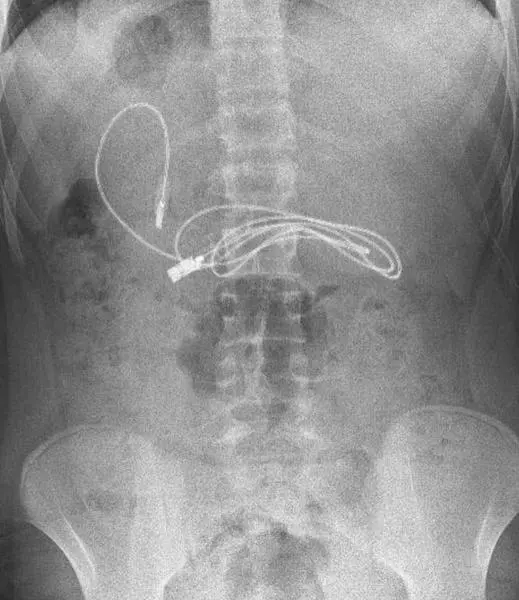

El cable USB y la goma del pelo dentro del joven

Asombrados quedaron los médicos de un hospital de Diyarbakir, en Turquía, después de descubrir que un adolescente de 15 años de edad tenía en el interior de su cuerpo un cable USB de casi un metro y una goma para el pelo. El menor había acudido al médico preso de los dolores estomacales, descubriendo por sorpresa, tras varias pruebas, que tenía algún objeto alojado en su interior.

El gastroenterólogo encargado de realizar la cirugía publicó en redes sociales las imágenes que muestran como estaba alojado el cable y la goma para el pelo dentro del joven, una vez ya fuera del menor. El médico realizó una endoscopía, a través de la boca, para llegar al lugar donde se encontraba alojado el cable, una tarea que fue bastante complicada: "Tuvimos dificultades para quitar el cable, ya que un extremo había pasado al intestino delgado".